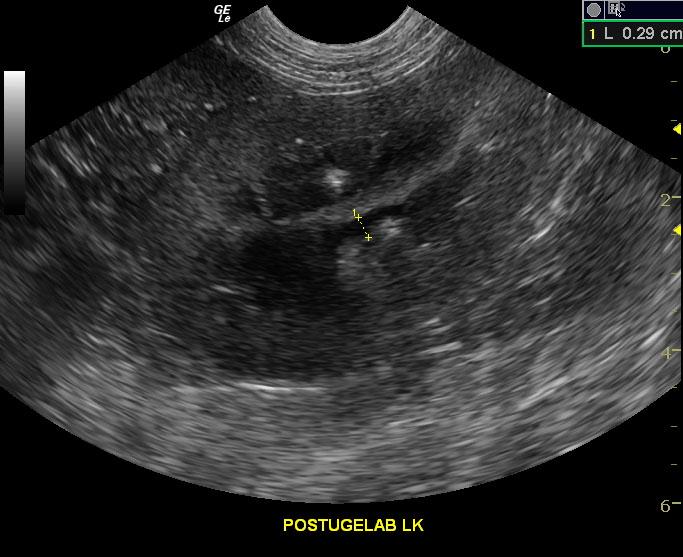

A 10-year-old SF American Eskimo with a history of bladder transitional cell carcinoma that had been stented, chronic renal insufficiency, hydronephrosis, and hydroureter, was presented for evaluation. CBC showed anemia (14%).